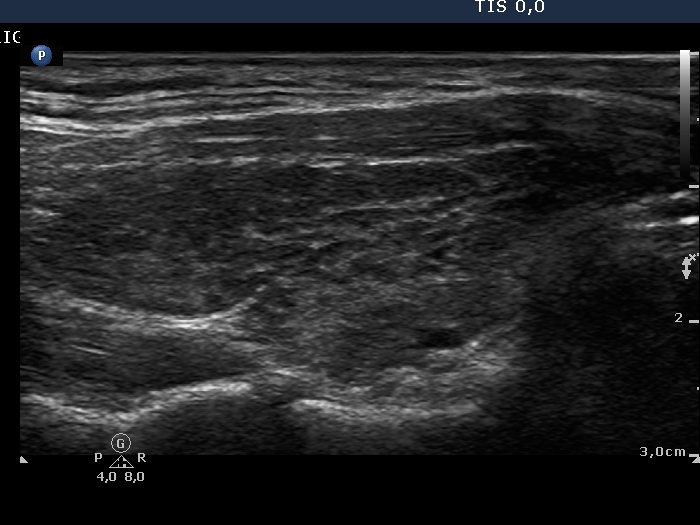

Chronic lymphocytic thyroiditis - Case 2. |

Clinical data: a 29-year-old woman was referred for an evaluation of a "suspicious nodule". She was examined on infertility. An elevated aTPO was found and a hyperechogenic nodule with microcalcification was described. FNAC was not diagnostic and surgery was advised.

Palpation: both thyroids were firm. No nodule was palpable.

Functional state: subclinical hypothyroidism with TSH 5.21 mIU/L, FT4 13.8 pM/L, aTPO 207 U/mL.

Ultrasonography: both thyroids were hypoechogenic with fibrotic changes. Based on the previously described "nodule", the fibrotic changes were more pronounced. This area did not fit a nodule.

FNAC disclosed Hashimoto's thyroiditis.